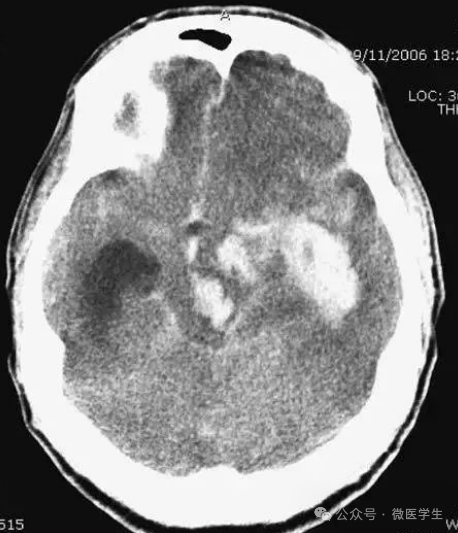

头部枪伤:

可见子弹轨迹,穿越大脑中线,

其毁灭性后果导致:

侧脑室积血,蛛网膜下腔出血,

脑积水(侧脑室颞角扩大),

小脑幕疝(脑干周围基底池消失或不对称)。